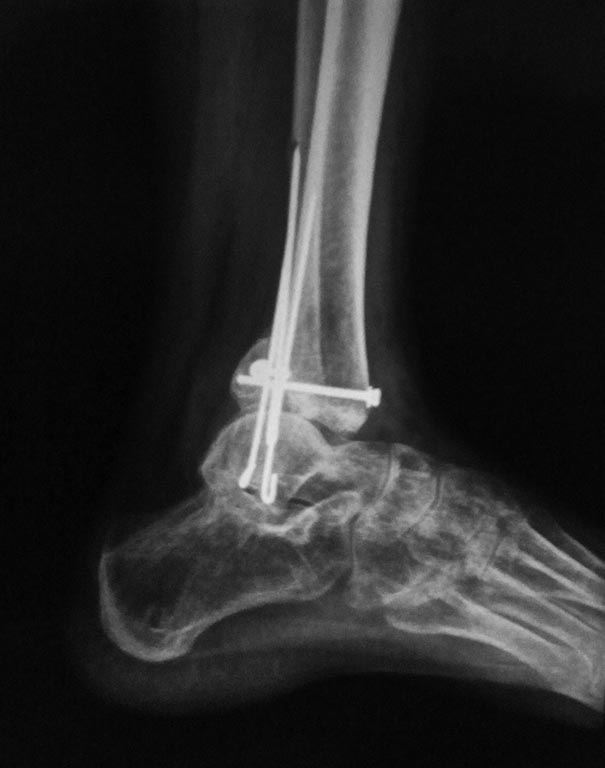

Мужчина, 1987 г.р. получил травму 10.2014. ДТП. Закрытый двухлодыжечный перелом костей костей левой голени, перелом заднего края большеберцовой кости с подвывихом стопы кзади, кнаружи.

Наложен дистрактор. Операция 10.2014: закрытая репозиция, остеосинтез спицами, винтами. В дальнейшем произошло ожидаемое усугубление нарушений взаимоотношений в голеностопном суставе.

Какой план лечения,на Ваш взгляд, предпочтительнее в данном случае? Возможно ли одномоментно устранить подвывих или только на аппарате Иллизарова? Первичные снимки после травмы отсутствуют. Критично ли "растоптана" латеральная суставная поверхность большеберцовой кости?

Мне кажется, что вопрос, поставленный Вами: "Возможно ли одномоментно устранить подвывих или только на аппарате Иллизарова?", отражает не совсем ясное понимание ситуации. Что значит устранить подвывих? А пластику ложных суставов внутренней лодыжки и заднего края большеберцовой кости не нужно делать? И ось голеностопного сустава нужно исправлять. То есть делать остеотомию наружной лодыжки (если она срослась, по снимку не очень понял). Артродез голеностопного сустава в такой ситуации очень сложен. Если же добиться сращения всех переломов в правильном положении, артродез вполне можно отсрочить на несколько лет, что для молодого пациента достаточно важно. Но в конечном счете все определяется Вашим умением и ясным представлением того, чего Вы хотите добиться своей операцией. Во вложении - в чем-то похожий случай. Оперировал эту пациентку 23 лет 11 лет назад через 8 месяцев после похожего на представленный Вами остеосинтез. На первой операции перелом малоберцовой кости в нижней трети был просто не замечен. За счет восстановления оси быстро развившийся артроз протекал благоприятно. В результате артродез был выполнен только в прошлом году, через 10 лет после второй операции. И боли беспокоили пациентку только в течение года перед артродезом.